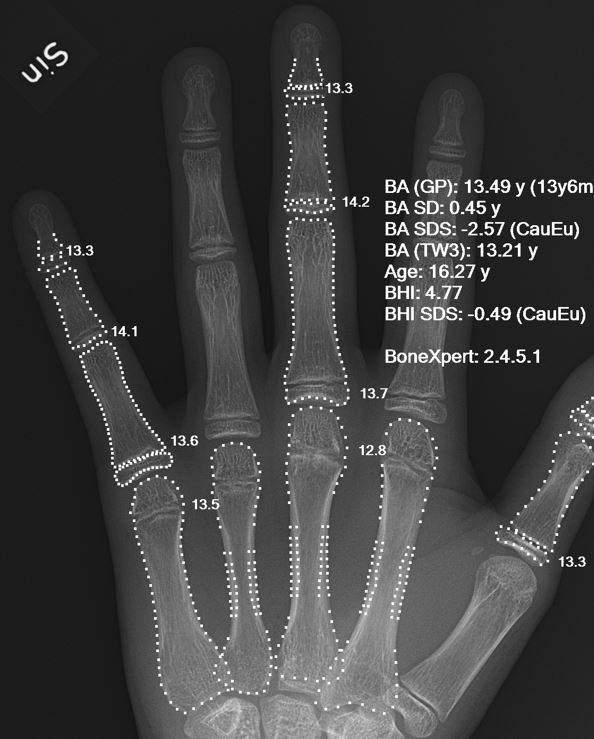

ورشة علمية الكترونية تحت عنوان «استخدام الذكاء الاصطناعي في تشخيص الامراض »

برعاية السيد عميد كلية المستقبل الجامعة الأستاذ الدكتور حسن شاكر مجدي المحترم و من اجل تحقيق اهداف التنمية المستدامة الهدف الرابع (التعليم الجيد) اقام المبرمج في قسم تقنيات البصريات مصطفى مرتضى خلف ورشة علمية الكترونية تحت عنوان «استخدام الذكاء الاصطناعي في تشخيص الامراض » وذلك في يوم الجمعة الموافق 24/3/2023.<br />